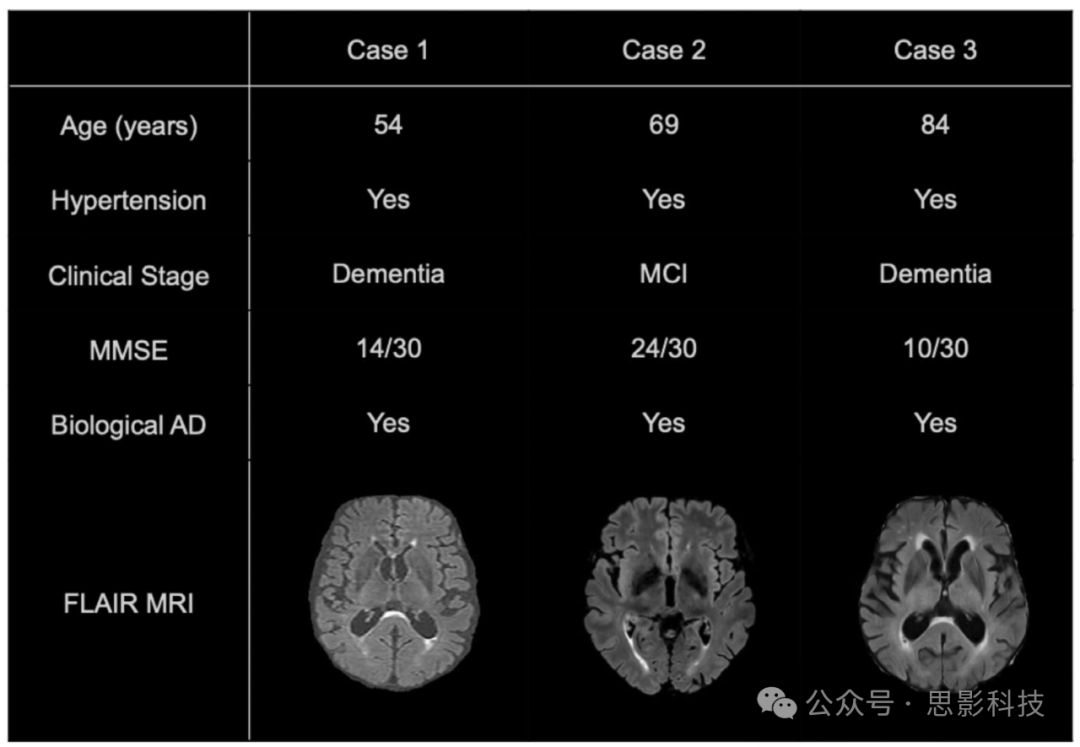

根据 2011 年美国老年医学研究所–阿尔茨海默病协会(NIA-AA)的建议:若有“显著并发脑血管病”的证据(部分以严重的 WMH 负担来界定),则不应将此患者诊断为“可能的 AD 痴呆,因为此时更可能的病因是血管性病变而非 AD。在出现大量或融合性 WMH 时(尤其是严重程度较高的情况),血管性病变的可能性相当高;然而,若这些 WMH 属于 AD 相关 WMH,则需谨慎评估在该患者中 “纯血管性因素” 是否被高估了。从患者个体角度看,WMH 可能部分或全部继发于单纯的血管性疾病,也可能是混合性疾病(AD+血管性认知障碍),或是“纯 AD”(见图 3)。如同 Brickman 等人于 2012 年所说,如果诊断标准将特定表现列为排除项,则可能会造成“用这些排除项来预先定义综合征病因的风险”,而不是从已知病因出发去构建更综合的诊断标准。因此,深入了解 AD 患者 WMH 的起源,对区分血管性与非血管性 WMH 至关重要;只有这样,才能更准确地判断痴呆的病因——既避免在血管性认知障碍中过度诊断 AD,也避免在实际上由 AD 相关 WMH 所致的情况下,错误地将其归咎为血管性病变,从而低估 AD 的诊断。

图 3 三个病例的临床、生物学与影像学特征这三位患者均符合临床-生物学 AD,具有血管风险因素(高血压)且存在中度 WMH。在这些例子中,WMH 可被视为脑血管疾病的替代性标志(surrogate),对认知功能产生额外损害(叠加假说),并/或在机制上与 AD 病理产生相互作用(交互假说)。另一种解释是,这些 WMH 中的一部分可能直接由 AD 病理所致,而不经过血管途径。那么,究竟他们患有“纯 AD”(其中 WMH 为 AD 所致)还是“混合性认知障碍”(AD+血管性认知障碍)?在 AD 进入可改变疾病进程的治疗时代,这一诊断对个体化干预尤为关键。三例患者中,脑脊液分析均证实 AD 生物学特征。

缩写:AD, Alzheimer’s disease;FLAIR, fluid-attenuated inversion recovery;MCI, mild cognitive impairment;MMSE, Mini-Mental State Examination;MRI, magnetic resonance imaging;WMH, white matter hyperintensities。